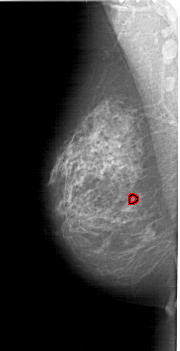

A_1632_1.LEFT_MLO

LEFT_MLO LINES 6316 PIXELS_PER_LINE 3226 BITS_PER_PIXEL 12 RESOLUTION 43.5 OVERLAY

FILE: A_1632_1.LEFT_MLO.OVERLAY

TOTAL_ABNORMALITIES 1

ABNORMALITY 1

LESION_TYPE CALCIFICATION TYPE PLEOMORPHIC DISTRIBUTION CLUSTERED

ASSESSMENT 4

SUBTLETY 2

PATHOLOGY BENIGN

TOTAL_OUTLINES 1

BOUNDARY